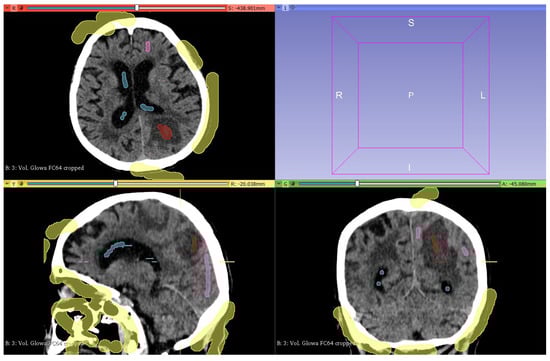

2.4.2. Segmentation

2.4.3. Model Creation and Visualization

2.4.4. Model Correction and Export